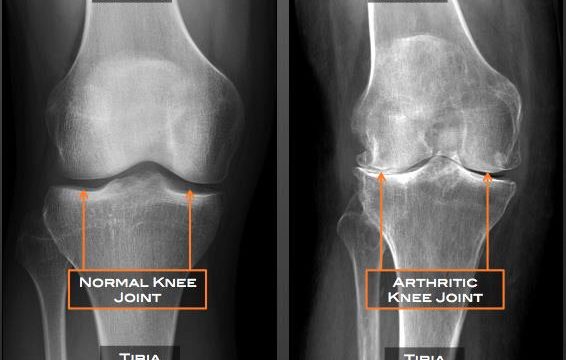

Knee Pain Arthritis Treatment

• Arthritis